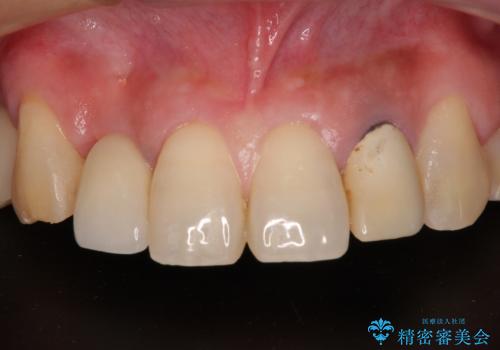

放置した破折歯 即時・早期のインプラント埋入による補綴治療

- 歯が破折しているため、抜歯が必要であると近医で診断されてからも放置を続けてしまったとのことで来院された患者様です。

セオリーとしては、インプラント補綴治療により奥歯の咬み合わせを確立してから、前歯部の処置を行うことになりますが、初めてのインプラント治療であることや、前歯部の見た目が気になっていることから、前歯の抜歯即時埋入インプラントによる補綴治療を先行して行い、並行して奥歯のインプラント治療を進めて行くこととしました。

抜歯即時埋入インプラントによる補綴治療の特徴は、短期間であることや処置数が少ないことが挙げられます。また、表側の歯肉の陥凹を避けることができるというメリットがあります。しかしながら、今回は歯根破折の程度が酷く、やや膨らみを失うこととなりましたが、スムーズに治療を終えることができました。